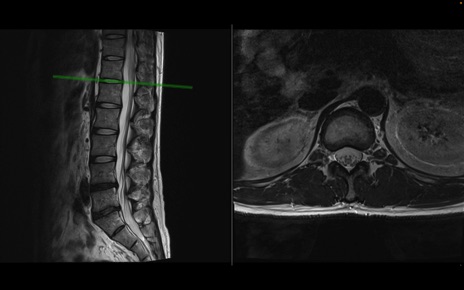

【整形】TIPS症例1 腰椎MRI 横断像と矢状断像

【症例】40歳代男性

【主訴】左臀部〜大腿後面痛み

【現病歴】2週間前から腰痛あり。2日前に夜中にくしゃみをした際に激痛が出現。疼痛強いため来院。

【身体所見】左臀部〜大腿後面、下腿後面のしびれ。SLR -/+ 30度、うつ伏せ困難、筋力低下なし。

異常所見と診断は?